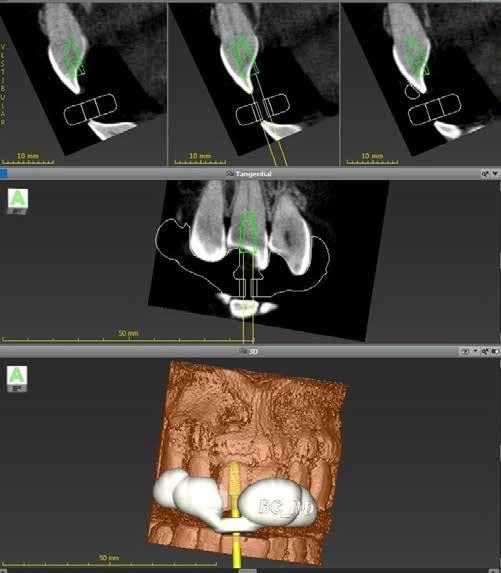

1. a-n. ábrák: Preoperatív CBCT-felvétel a bal alsó 6-os (3.6) fogról. Az axialis (a), coronalis (b) és sagittalis (c) nézeteken a mezialis és distalis gyökerek apicalis harmada körül sugáráteresztő zóna és ép buccalis corticalis csont látható. Egy olyan sablont terveztünk, amely jelezte a csontablak határait az apicalis terület pontos elérése érdekében (d). A mikrosebészeti bevatkozás során a sablont a helyére illesztettük (e), a csontablak határait megjelöltük (f) egy Piezotome CUBE LED kézi-darabba fogott fűrésszel, majd kivágtuk és eltávolítottuk (g és h) az apicalis területhez történő hozzáférés, illetve a mezialis és distalis gyökerek rezekciójának, retrográd preparációjának és retrográd gyökértömésének elvégzése érdekében (i). Végezetül a csontablakot visszaillesztettük és kollagén szivaccsal stabilizáltuk (j). A műtét után közvetlenül készített röntgenfelvétel a 3.6-os fogról (k). A kétéves kontroll során készített CBCT-felvétel: axialis (l), coronalis (m) és sagittalis (n) nézetek.

Egy 63 éves páciens korábban már kezelt bal alsó első nagyőrlőfogából (3.6) eredő mérsékelt fájdalom miatt kereste fel rendelőnket. A kórtörténetében panasza szempontjából releváns információ nem szerepelt. Az elkészült CBCT-felvételen a korábbi kezelések során észre nem vett, jelenleg feltáratlan meziobuccalis csatornát, valamint a mezialis és distalis gyökerek körül kialakult periapicalis elváltozást, és ezt a léziót borító intakt buccalis corticalis csontlemezt láttunk.

Klinikai vizsgálat során vertikális kopogtatási érzékenységet jelzett. A fog körül mérhető szondázási mélység és a fogmobilitás fiziológiás volt. A CBCT-felvételen nem észleltünk a csontos regeneráció megindulására utaló jeleket (1. a–c. ábrák). A korábban gyökérkezelt, gyökértömött és revideált 3.6-os fog esetében az alábbi diagnózis került felállításra: periodontitis periapicalis symptomatica. A panaszokat okozó fog további ellátása során navigált endodonciai mikrosebészetet kívántunk alkalmazni. Az alsó állcsontról intraorális szkent (TRIOS, 3Shape) készítettünk, és a felszíni topográfiát tartalmazó STL fájlt, valamint a CBCT-felvétel készítése során nyert DICOM fájlokat a Blue Sky Bio szoftver segítségével egyesítettük. A sebészi sablon megtervezésére az így kapott háromdimenziós képet használtuk. A sablon kialakítása során arra törekedtünk, hogy a sablon egyértelműen meghatározza a gyökércsúcsi terület eléréséhez szükséges csontablak határait (1. d. ábra)

A beavatkozás során helyi érzéstelenítésben teljes vastagságú mucoperiostealis lebenyt képeztünk, és a sablon segítségével bejelöltük a preparálandó csontablak határait. Az ablak széleinek megfelelően Piezotome CUBE LED kézi-darabbal (ACTEON) a kortikális teljes vastagságában vágást ejtettünk, majd az így kapott csontlemezt (ablakot) eltávolítottuk (1. e–h. ábra), és ezt követően steril fiziológiás sóoldatba helyeztük. A rezekció elvégzését követően (1. i. ábra) a mezialis csatornákat ultrahangos eszközök segítségével (NSK) retrográd irányból preparáltuk, majd az így kialakított mélyedésbe retrográd gyökértömést készítettünk. A tömés anyagául az EndoSequence BC RRM Fast Set Putty-t (Brasseler) választottuk. A tömés elkészítését követően a csontablakot visszaillesztettük, és a stabilizálása érdekében a vágásoknak megfelelően kialakult résekbe kollagén szivacsokat (Collagen Tape, Zimmer Biomet) helyeztünk (1. j-k. ábra). A lebenyt 6/0-s Prolene varratokkal (Corpaul) rögzítettük.

A kétéves kontroll során elvégzett klinikai és radiológiai vizsgálat (CBCT-felvétel) a periapicalis elváltozások megszűnését és a corticalis csontállomány tünet- és szövődménymentes gyógyulását